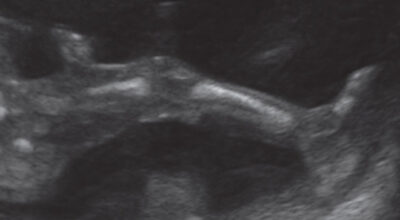

La evolución del feto a través de ecografías

Ecografía de 23 semanas: examen de la columna vertebral y las costillas a través de la ecografía 3D. Este análisis no es sistemático y se realiza cuando hay cierta susceptibilidad de una anomalía de las vértebras o una enfermedad ósea.